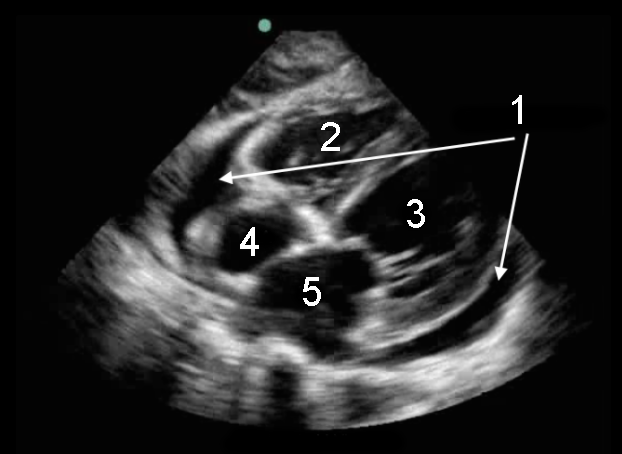

Heart Subxiphoid Fluid Image

1. Pericardial Fluid

2. Right Ventricle (RV)

3. Left Ventricle (LV)

4. Right Atrium (RA)

5. Left Atrium (LA)